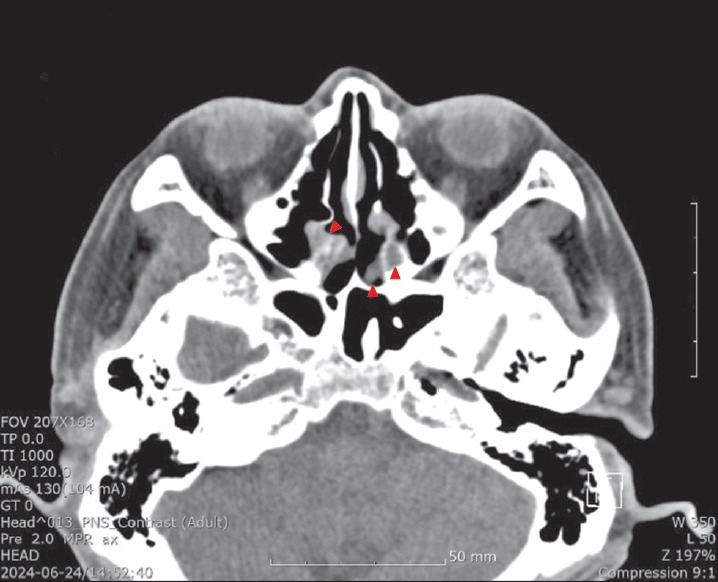

连续性偏头痛(HC)是一种吲哚美辛反应性头痛,以单侧和持续头痛为特征,伴有颅自主神经症状。各种病理,包括鼻窦相关疾病,都与HC有关。在这里,我们报告一个62岁男性丙型肝炎和鼻窦炎的病例。患者主诉单侧持续头痛伴同侧颅自主神经症状,结膜注射和眼睑水肿20个月。根据症状标准,HC被确定为潜在的诊断,对吲哚美辛的反应证实了诊断。伴有单侧头痛和颅自主神经症状的患者应考虑三叉神经自主神经性头痛。

Hemicrania continua (HC) is an indomethacin-responsive headache, characterized by unilateral and continuous headaches with cranial autonomic symptoms. Various pathologies, including sinus-related conditions, are associated with HC. Here, we report the case of a 62-year-old man with HC and rhinosinusitis. The patient complained of a unilateral continuous headache with ipsilateral cranial autonomic symptoms, conjunctival injection, and eyelid edema for 20 months. HC was identified as a potential diagnosis based on the symptom criteria, and a response to indomethacin confirmed the diagnosis. Trigeminal autonomic cephalalgia should be considered in patients with unilateral headaches and cranial autonomic symptoms.